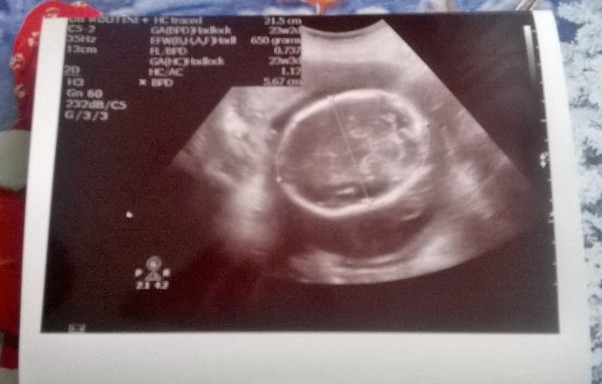

Dzisiejsza wizyta kontrolna u lekarza prowadzącego ciążę potwierdziła dane odnośnie płci maleństwa. Dodatkowo dowiedziałam się że maluch waży juz 650 g. Zobaczyłam wszystkie części jego ciałka a nawet posłuchałam serduszka. Piękne przeżycie. Na zdjęciu główka maleństwa.